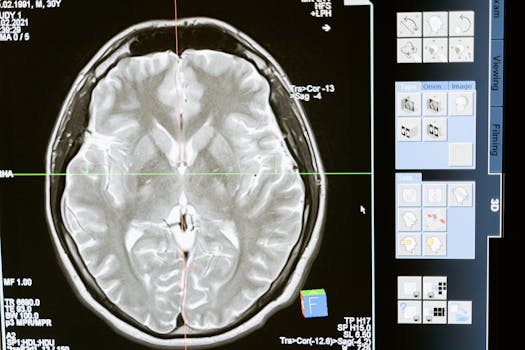

One of the most exciting areas within cranial technologies is diagnostic imaging. Gone are the days of just basic X-rays for complex brain issues. We’re now seeing advanced MRI techniques, PET scans that can visualize metabolic activity, and even sophisticated neurophysiological assessments that provide a detailed, real-time look at the brain’s intricate workings.

High-Resolution MRI: Offering incredibly detailed anatomical views, allowing for the detection of minuscule anomalies.